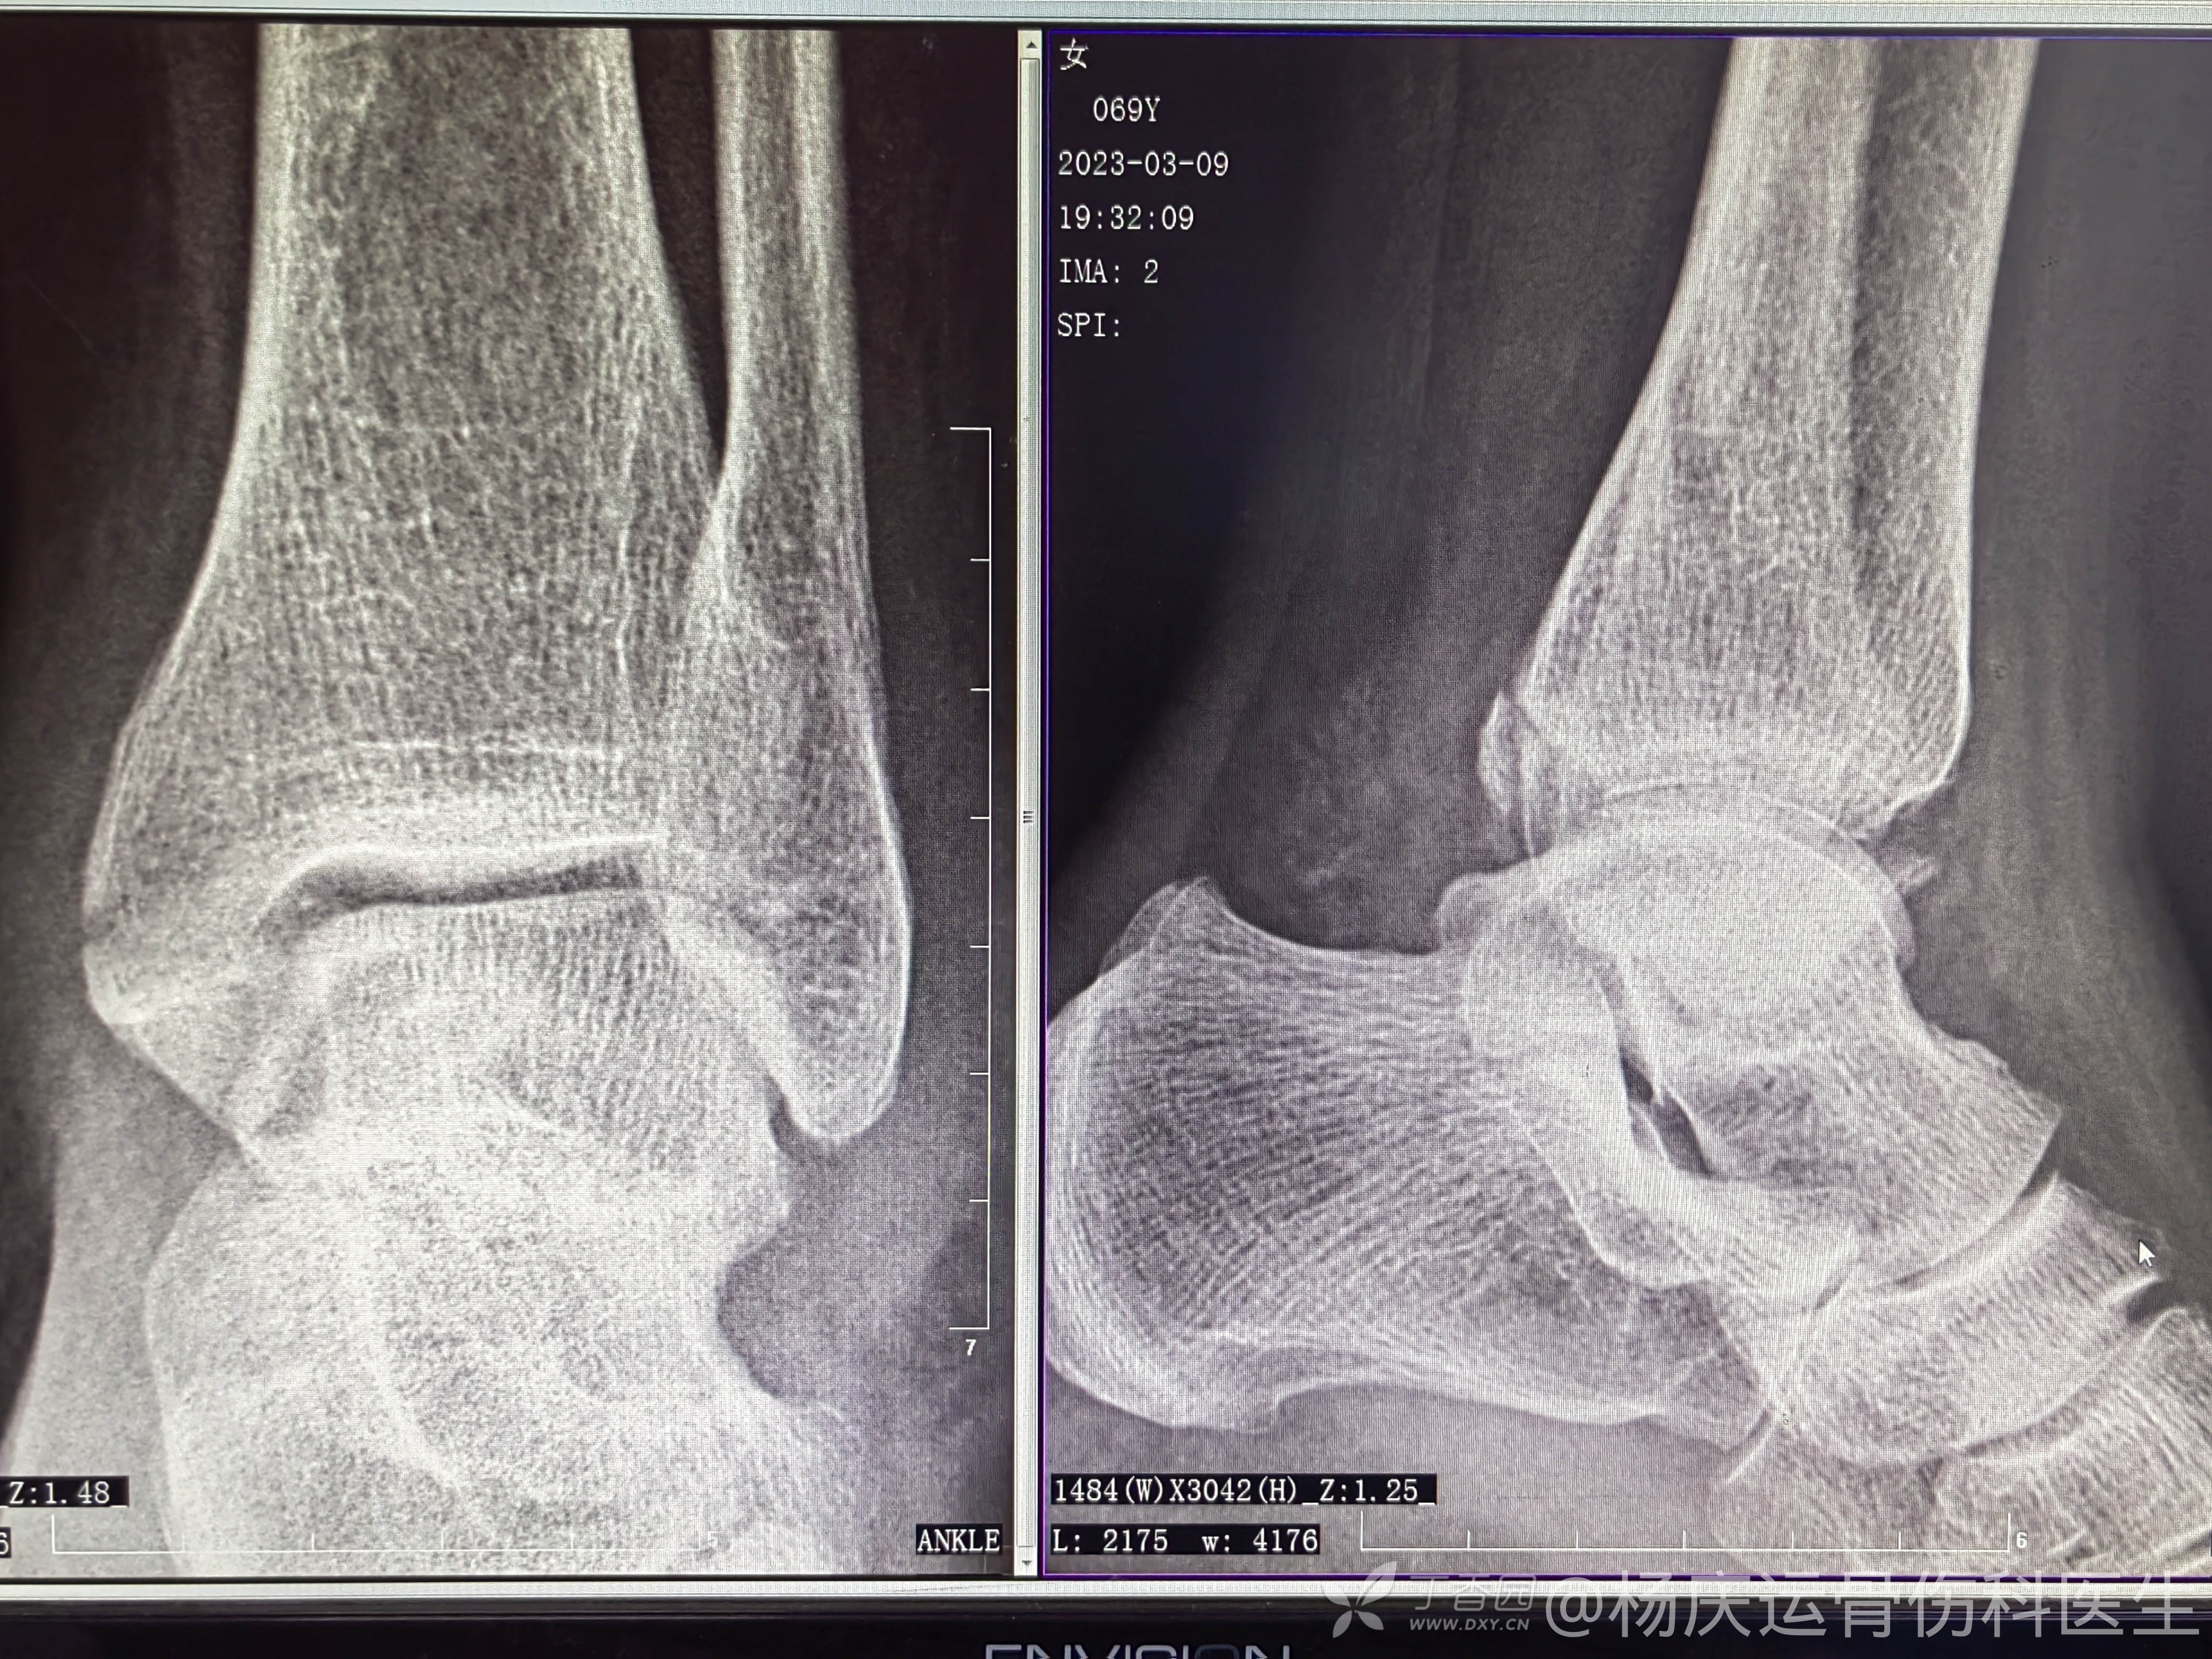

复位前DR片